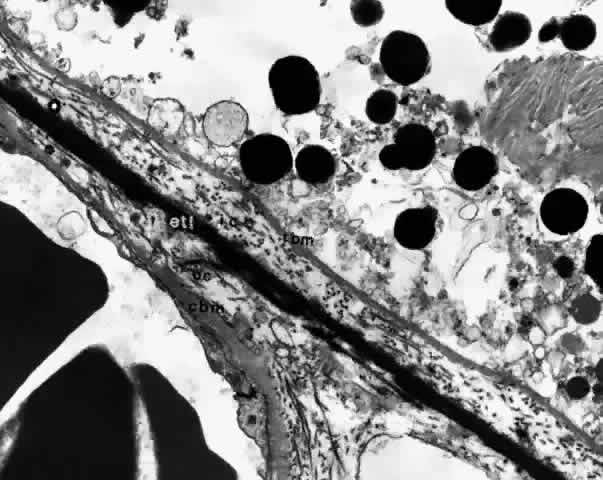

membrane is formed of five layers: the basement membrane of the RPE, the inner collagenous zone, the elastic tissue layer, the outer collagenous zone, and the basement membrane of the choriocapillaris (Fig. 8).  Fig. 8. Bruch's membrane. Basement membrane of retinal pigment epithelium (rbm), inner collagenous zone (ic), elastic tissue layer (etl), outer collagenous zone (oc) and basement membrane of choriocapillaris (cbm). (× 14,500) Fig. 8. Bruch's membrane. Basement membrane of retinal pigment epithelium (rbm), inner collagenous zone (ic), elastic tissue layer (etl), outer collagenous zone (oc) and basement membrane of choriocapillaris (cbm). (× 14,500)

Ultrastructurally, the basement membrane of the RPE and choriocapillaris

is made of fine filaments that blend with the collagen of the adjacent

collagenous zones. The basement membrane of the RPE is separated from

the cytoplasmic membrane of the RPE, from which it is derived, by a 100 nm

radiolucent zone. The cytoplasmic membrane of the RPE cell has

many infoldings, which its basement membrane usually does not follow, although

it may project slightly into the outer part of some folds.22,23 The basement membrane of the RPE is continuous with the basement membranes

to the pupillary edge of the iris. The basement membrane of the choriocapillaris

is discontinuous at the intercapillary septa. The inner and outer collagenous zones are made up of randomly oriented

collagen fibers measuring 60 nm in diameter. Many are parallel to the

retina, and others pass from the inner collagenous zone through the elastic

layer into the outer collagenous zone. At the ora serrata, the inner

collagenous layer thickens, displacing the elastic layer outwardly. The elastic layer, the middle layer of Bruch's membrane, is a dense, irregularly

interrupted band composed of interwoven elastic tissue

fibers of various thickness. The elastic fibers are ultrastructurally

composed of long and straight rods with a homogeneous core and dense cortex. Variably

sized spaces are present between the elastic fibers. They

provide passageways for collagen fibers from the inner collagenous

zone to the outer collagenous zone and into the intercapillary septa

and subcapillary zone of the choriocapillaris (Fig. 10). The elastic tissue and collagenous layers of Bruch's membrane become